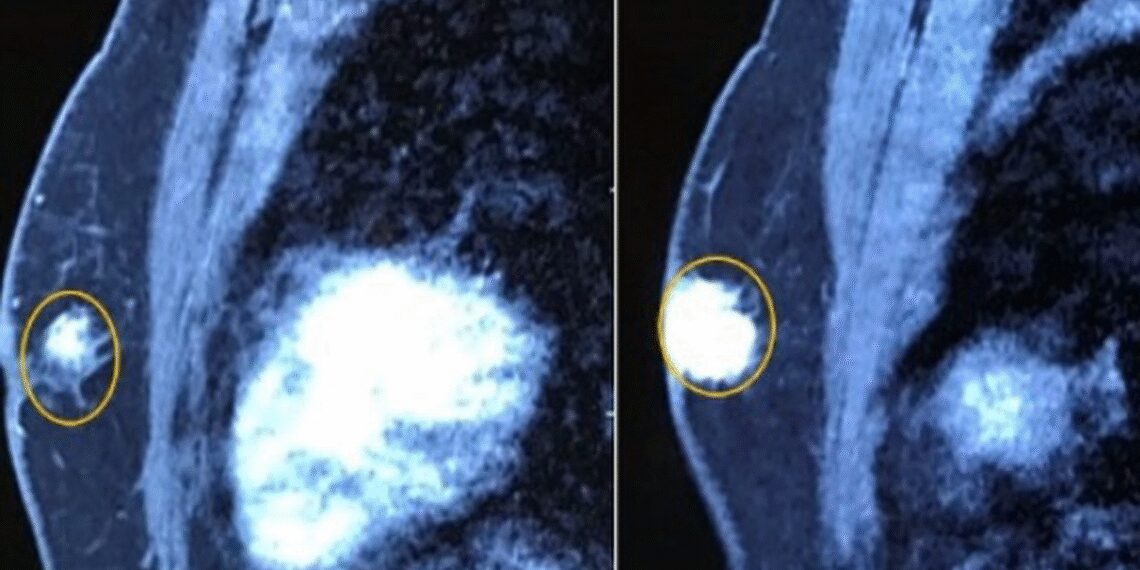

Tuyến vú trái có khối u kích thước 2×2,5cm, chắc, ranh giới không rõ, còn di động.

Hình ảnh chụp cộng hưởng từ tuyến vú có khối u ngay dưới núm vú trái kích thước 21x28mm, chưa xâm lấn cơ thành ngực, co kéo núm vú (Ảnh: B.V).

Bệnh nhân được chỉ định cắt toàn bộ tuyến vú trái, vét hạch. Sau hậu phẫu bệnh nhân ổn định sẽ tiếp tục điều trị các liệu pháp toàn thân (hóa trị, nội tiết…) kết hợp với điều trị và theo dõi bệnh lý về tim mạch.